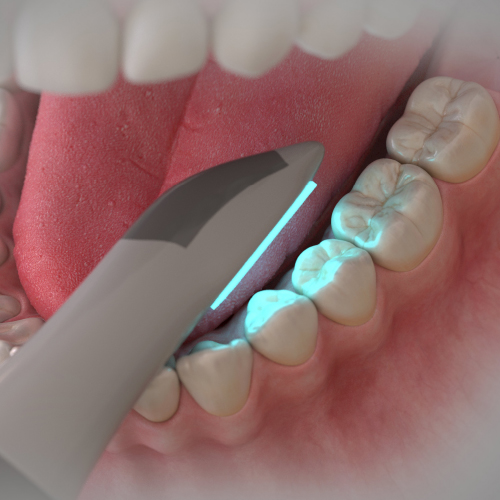

Handheld Curing Lasers and Other Modalities to Increase the Clinical Efficiency of Bonding Procedures

Tuesday, December 20, 2022

This Compendium eBook offers a continuing education (CE) article that discusses various modalities and processes that clinicians can employ, such as the use of handheld curing lasers, to increase the clinical efficiency of bonding procedures and thus help mitigate postoperative sensitivity ...